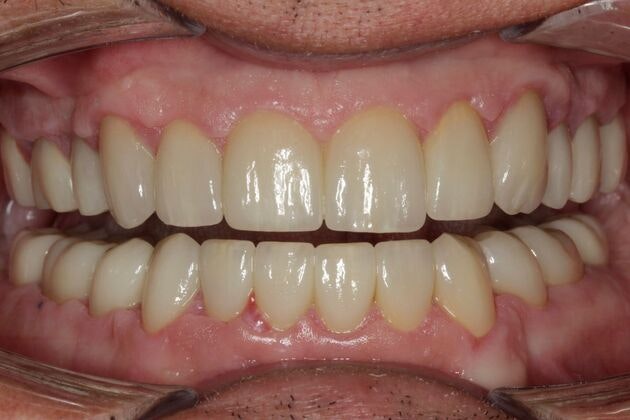

A smile has an incredible influence not only on how you are perceived by others, but how you perceive yourself. A healthy, beautiful mouth is much more than simply straight, white teeth. It involves a proper bite relationship (occlusion), joint and muscle comfort (TMJ), and proper soft tissue (gum) health. Our Vernon and Coventry, CT, dentists are dedicated to providing cosmetic dentistry and restorative procedures that can restore your smile to optimum health and appearance.

Our dentists accomplish this goal by developing individualized treatment plans based on your specific clinical needs and incorporating your own dental goals. This systemic approach involves exceptional care and time. If necessary, our dentists will work with the best specialists in the area to provide you the dental care you need.